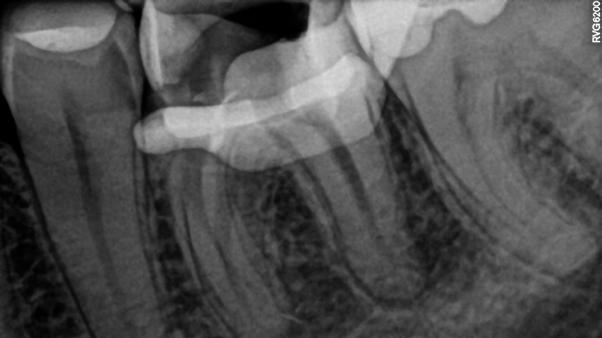

A páciens a jobb alsó első nagyőrlőfogából kiinduló közepes erősségű fájdalom miatt kereste fel a rendelőnket. Periapikális röntgen és CBCT-felvétel is készült. Mindkét felvétel a mesiobukkális gyökércsúcs körül található radiolucens elváltozás jelenlétét igazolta. Ezenfelül a mesialis gyökérben két betört eszközdarab is észlelhető volt. Az egyik a középső gyökéri harmadban a gyökérgörbület előtt volt megtalálható, a másik pedig kicsivel a gyökérgörbület után (12–13. ábra).

A terület érzéstelenítését és kofferdám felhelyezését követően a meglévő kompozittömést eltávolítottuk és a gyökértömés elkészítéséhez szükséges körülmények biztosításához folyékony kompozit és folyékony kofferdám felhasználásával egy ideiglenes felépítményt készítettünk (14–17. ábra). Ezt követően eltávolítottuk a gyökértömő anyagot a mesialis és a disztális gyökércsatornákból. A betört eszközökhöz való hozzáférés biztosítását követően a magasabban elhelyezkedő fragmentumot egy ultrahangos eszköz segítségével eltávolítottuk (18. ábra). Ezután a mélyebben fekvő darab koronális vége is láthatóvá vált. Sajnos az eltávolítandó gyökérkezelő tű a közepén kettétört és csak a koronálisabban fekvő részét sikerült eltávolítani (19. ábra). Mivel az apikális fragmentumra nem láttunk rá közvetlenül és az átöblítés, valamint aktiválás hatására sem emelkedett ki a csatornából, ezért az eszköz mellett történő elhaladás megkísérlése mellett döntöttünk. A CBCT-felvétel tanulmányozása során nem tudtuk egyértelműen megállapítani, hogy a két mesialis csatornának vajon egy közös vagy két különálló kivezetőnyílása van, ezért a mesiolingualis csatorna megmunkálása közben periapikális röntgenfelvételt készítettünk. A röntgenfelvétel alapján vagy egy lépcső-

12. ábra: A kiindulási CBCT-felvételen jól látható a periapikális felritkulás. – 13. ábra: A kiindulási röntgenfelvételen látható a két betört eszközdarab.